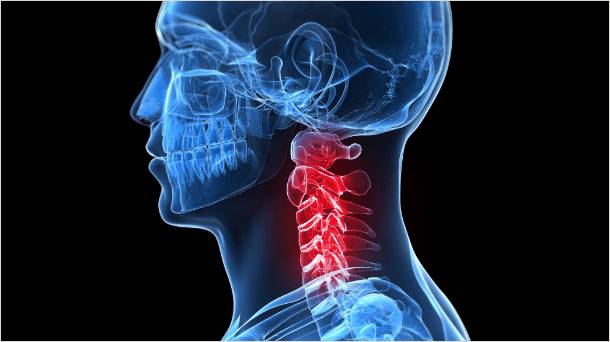

일자목, 거북목

외부 충격이나 반복적인 행동 습관 때문에 목뼈의 굽어져 있는 배열이 비정상적으로 펴지는 경우가

있는데,

이것을 일자목(거북목)이라고 합니다.

일자목

정상적인 목뼈는 C자형으로 머리의 무게를 여러 방향으로 분산시켜 줍니다. 또한, 이 C자형 곡선은 용수철처럼 탄성을 가지고 있기 때문에 외부의 충격을 분산시킬 수 있습니다. 일자목은 충격 완화 능력이 떨어져 외부 충격이 분산되지 않고 목과 머리, 어깨에 직접 전달되며 목의 특정부위에 하중이 집중되어 목디스크가 오거나 퇴행성 질환이 생길 수 있습니다.